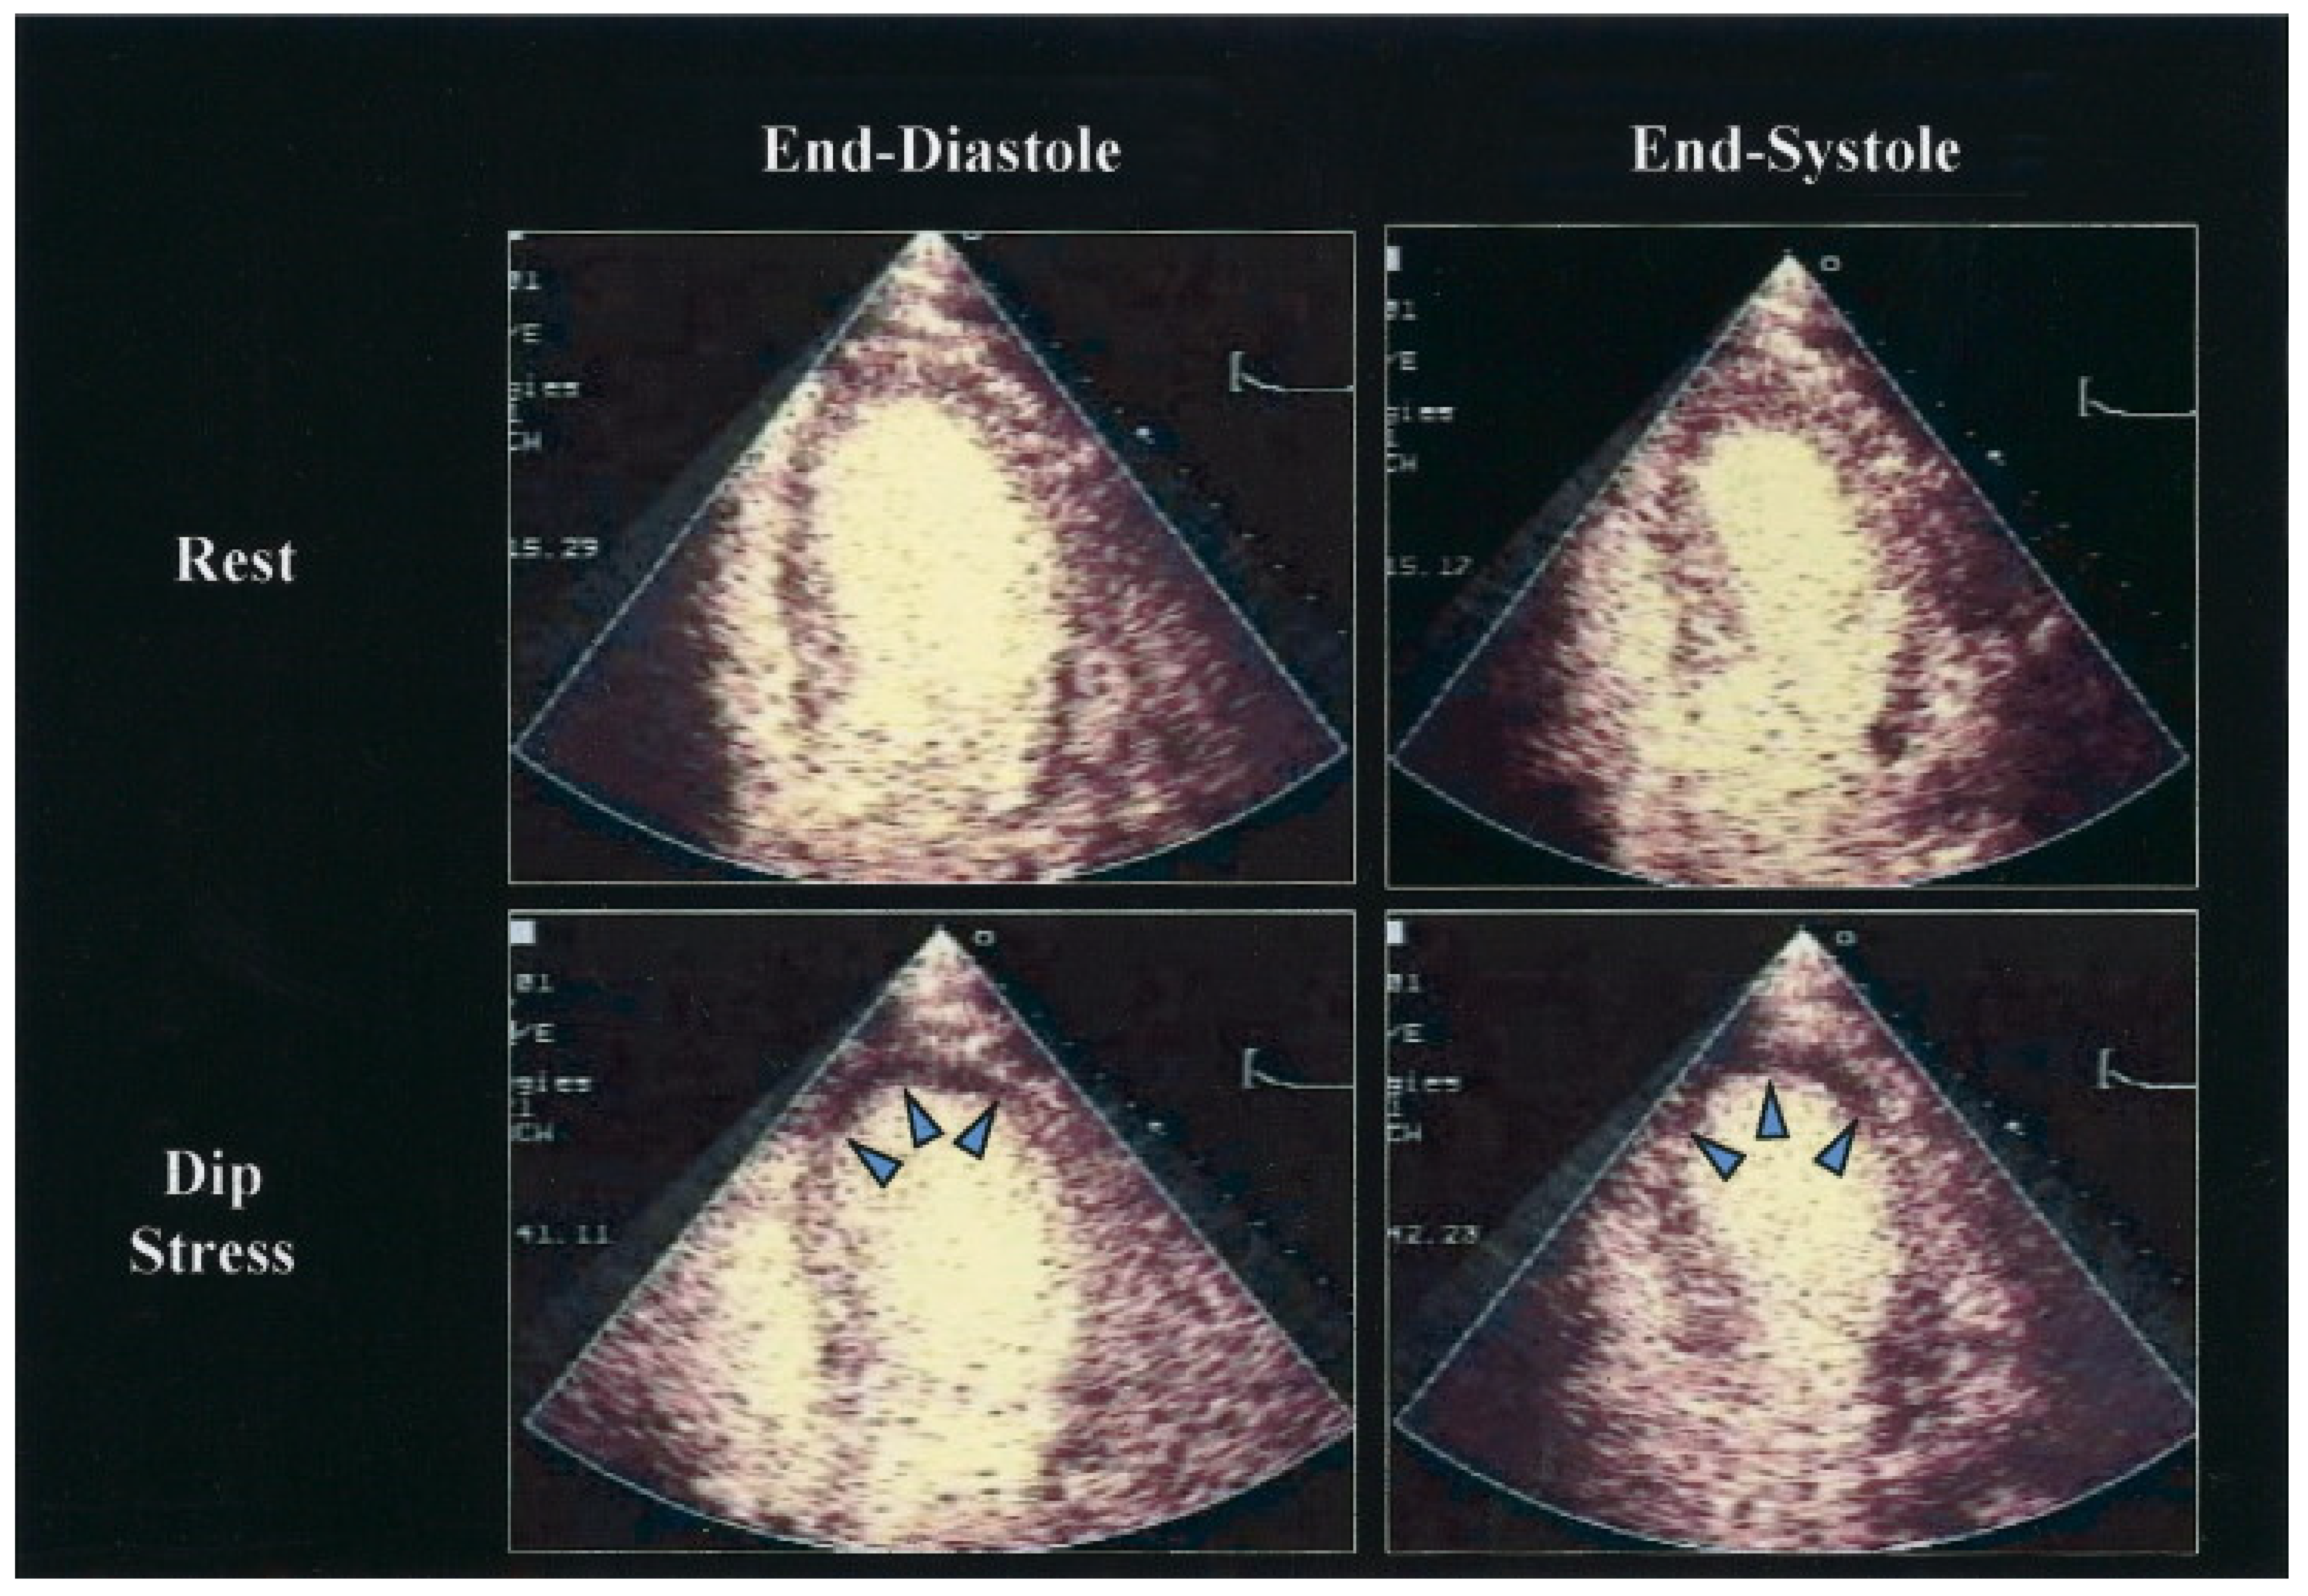

6. Stress Echocardiography

6.3. Myocardial Viability Assessment